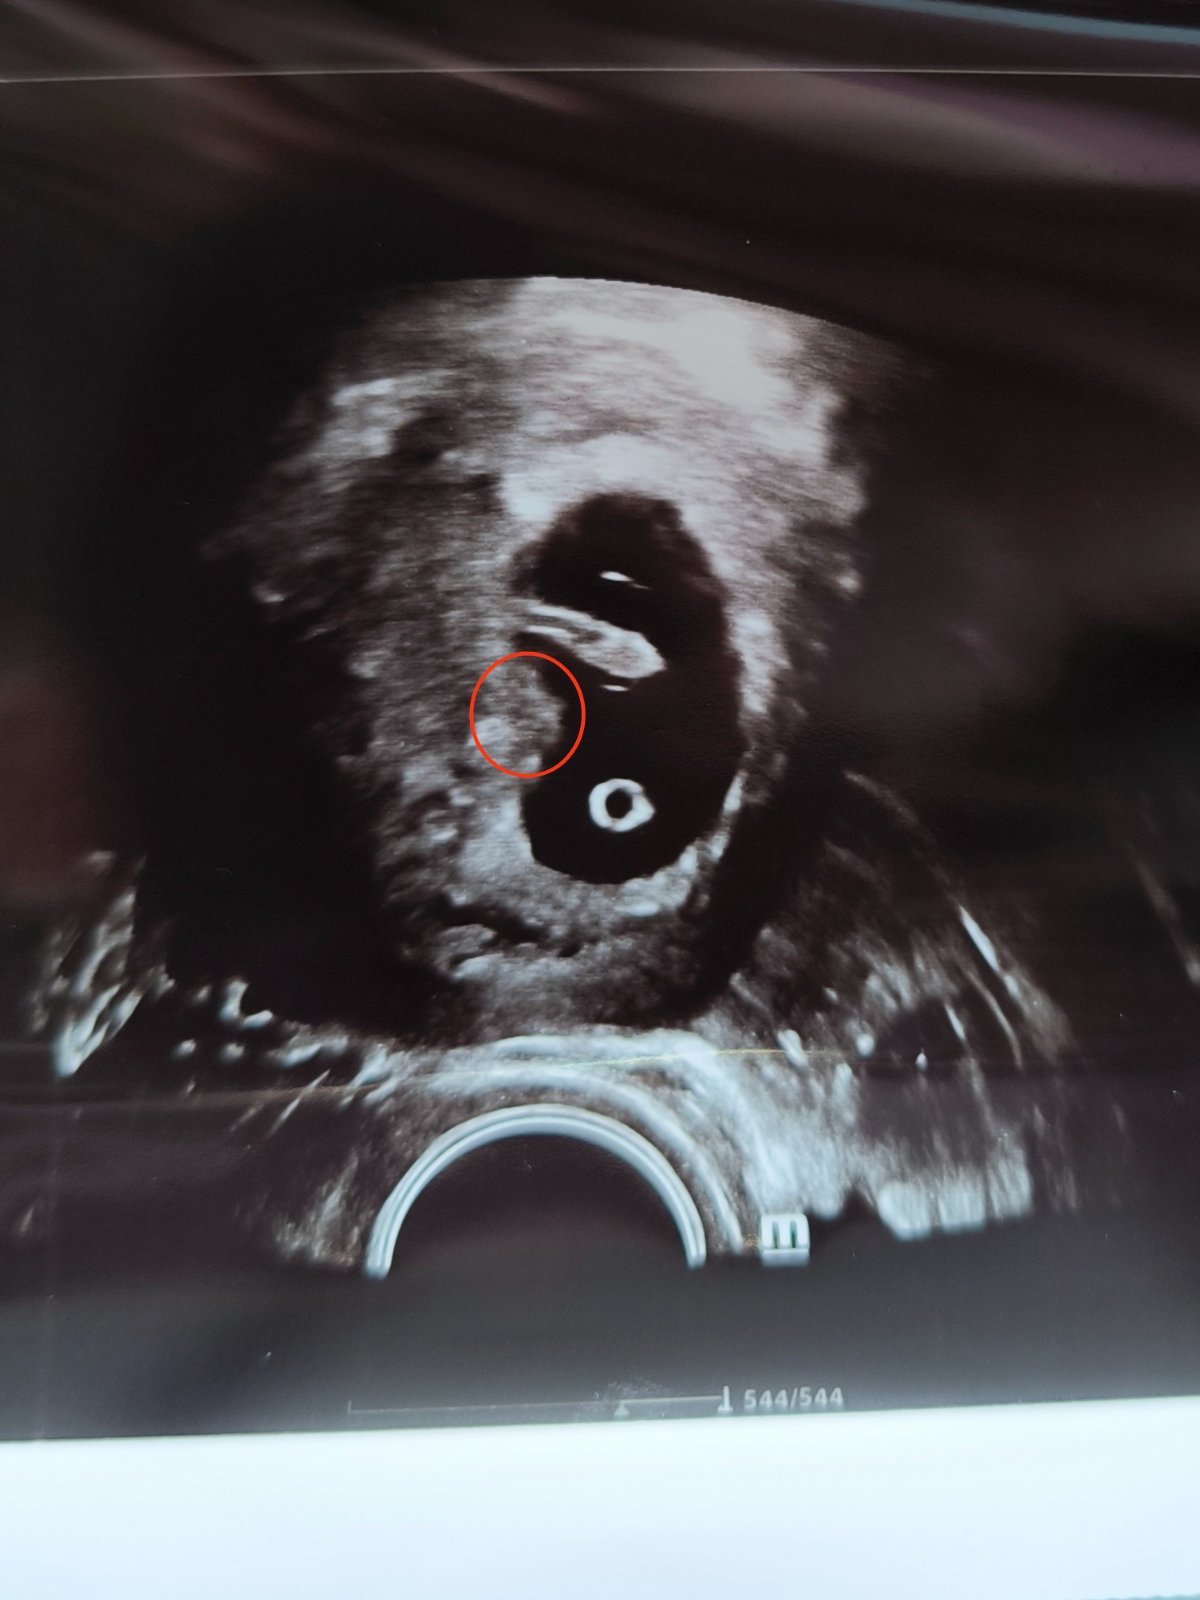

Sono v 8. týždni

Ahojte, včera som bola na sone, doktorka mi povedala že ie všetko ok, len ma zaujíma keď som si doma pozerala fotku, že čo to je za zhluk buniek naľavo pod embryom na tej fotke. Môze to byť vyvíjajúca sa placenta? Ak je tu niekto kto sa v tom vyzná, že by mi povedal čo to je.

@natalis1998 áno, tá gulička dole je žĺtkový vak, ale naľavo nad tou guličkou je čo? Myslím ako y na stene toho gestačn3ho valu, pod embryom